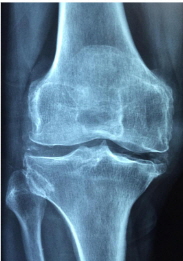

골다공증은 간단하게 말하면 뼈에 밀도가 떨어지도 양이 적어지면서, 뼈에 강도가 약해지는 증상을 일컫습니다. 이렇게 뼈가 약해지게 되면 골절이 일어날 가능성이 크게 증가하게 됩니다.

뼈의 밀도는 세계보건기구에서 정의 내린 것을 확인하면, 성인 평균치의 2.5 표준편차 이하의 골밀도를 골다 골증으로 정의를 내리고 있습니다.